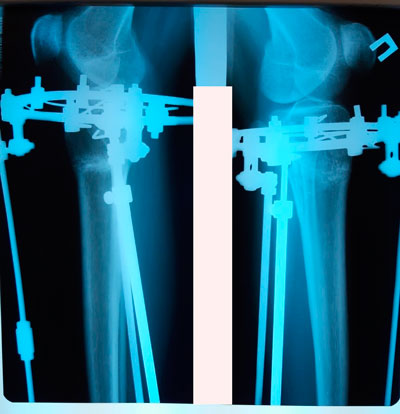

Пациентка - 30 лет.

Дата операции - 04.04.2019г.